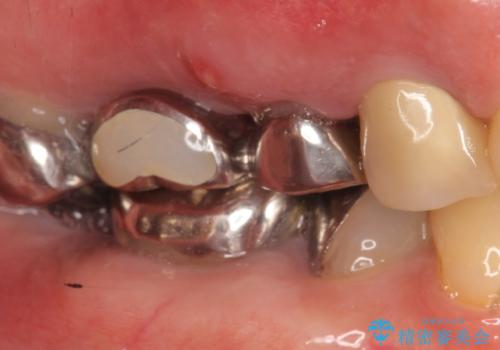

- 右上のブリッジでものを咬むと違和感があり、歯茎に膿の出口もできているので診て欲しいといらっしゃった方の症例です。

右上の567ブリッジを外したところ、右上5は歯根破折により保存不可能だったため、右上56部にインプラントを埋入し欠損補綴を行いました。

また右上5部に関しては抜歯時に歯槽堤保存術(抜歯窩に人工骨の填入を行う手術)を行い、骨の欠損を最小限に止めています。